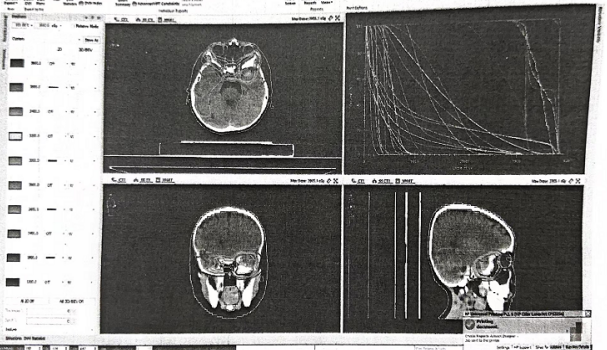

2022年4月患儿出现头痛,完善头部核磁提示左侧中颅窝底占位性病变(3.6*2.9cm)。

PET-CT:左侧眼眶后壁骨质改变,伴灶周软组织肿块突向左侧眼眶后壁及左侧颞叶,考虑转移。

头部MRI检查(2023.03.17):

左侧蝶骨大翼区及邻近颞叶未见异常强化,提示达到完全缓解(CR)。

头部MRI增强(2024.06、2026.01):

未见明显异常。